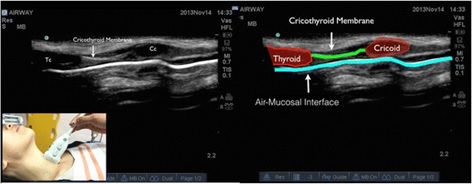

Debido a la diferencia en impedancia acústica entre los tejidos blandos y el aire, las ondas sonoras se reflejan con intensidad (se ve blanco), por lo que en la interface entre aire y mucosa se aprecia una línea blanca intensa.

Pasos para identificar la membrana cricotiroidea:

- Hay que usar un transductor lineal (mejor resolución para estructuras superficiales).

- El transductor se ubica en posición longitudinal sobre la tráquea, con el marcador hacia arriba.

- Los anillos traqueales se identifican como pequeñas pelotitas ovaladas hipoecogénicas (figura 4). Una vez encontrados, hay que ascender un poco.

- Hacia el “final” de los anillos traqueales uno va a encontrar una zona hipoecogénica de un tamaño discretamente mayor que los anillos, correspondiente al cartílago cricoides.

- Si uno sigue ascendiendo, hay una zona discretamente deprimida seguida de una estructura ovalada hipoecogénica. Estas corresponden a la membrana cricotiroidea y al cartílago tiroides respectivamente (figura 5).

- No siempre se logra ver la membrana cricotiroidea en forma íntegra, por lo que la clave es detectar los cartílagos cricoides y tiroides. Ya habiendo encontrado la membrana, es prudente marcarla con un lápiz u otro.